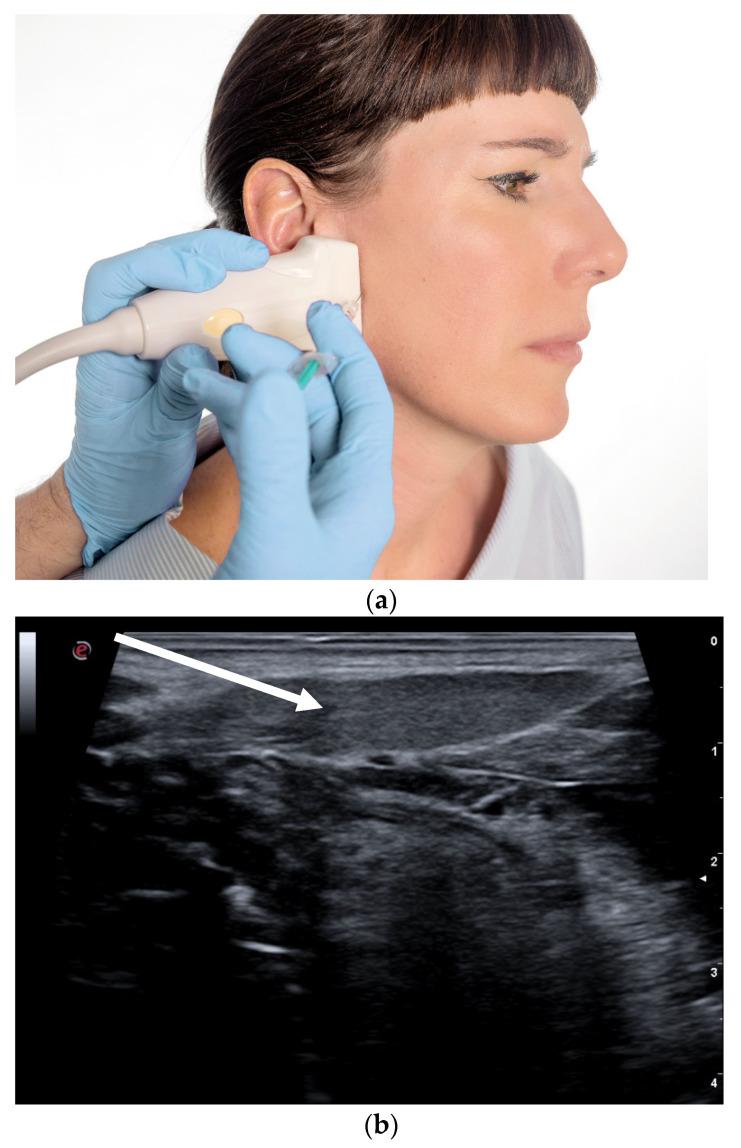

https://cdn.ncbi.nlm.nih.gov/pmc/blobs/89bb/7910947/bc36a2283d0e/toxins-13-00087-g001.jpg